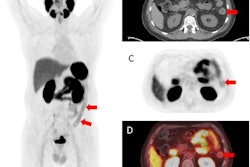

Contrast-enhanced MRI provides better visualization of the entire bowel wall in comparison to conventional T2-weighted imaging. The researchers sought to apply radiomics to the task of distinguishing between ulcerative colitis and Crohn's disease on these MRI exams.

They retrospectively gathered data from 216 IBD patients who had received colonoscopy and contrast-enhanced MRI between 2012 and 2021 at their institution. Of these, 116 had ulcerative colitis and 100 were diagnosed with Crohn's disease.

Next, the researchers used the PyRadiomics software to extract 1,037 radiomics features from manually drawn regions of interest on the images that depicted abnormally thickened intestinal walls. The radiomics features included first-order, texture, and shape features. A least absolute shrinkage and selection operator (LASSO) regression model was then employed to select the 15 best radiomics features and build a radiomics "signature."